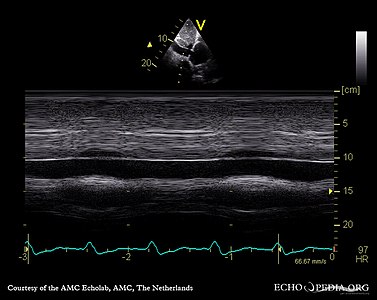

If pulmonary hypertension is suspected based on the above assessments, echocardiography is performed as the next step.[10][11][53] A meta-analysis of Doppler echocardiography for predicting the results of right heart catheterization reported a sensitivity and specificity of 88% and 56%, respectively.[55] Thus, Doppler echocardiography can suggest the presence of pulmonary hypertension, but right heart catherization (described below) remains the gold standard for diagnosis of PAH.[10][11] Echocardiography can also help to detect congenital heart disease as a cause of pulmonary hypertension.[10]

Although pulmonary arterial pressure (PAP) can be estimated on the basis of echocardiography,[60] pressure measurements with a Swan-Ganz catheter inserted through the right side of the heart provide the most definite assessment.[42] Pulmonary hypertension is defined as a mean PAP of at least 20 mm Hg (3300 Pa) at rest, and PAH is defined as precapillary pulmonary hypertension (i.e. mean PAP ≥ 20 mm Hg with pulmonary arterial occlusion pressure [PAOP] ≤ 15 mm Hg and pulmonary vascular resistance [PVR] > 3 Wood Units).[53] PAOP and PVR cannot be measured directly with echocardiography. Therefore, diagnosis of PAH requires right-sided cardiac catheterization. A Swan-Ganz catheter can also measure the cardiac output; this can be used to calculate the cardiac index, which is far more important in measuring disease severity than the pulmonary arterial pressure.[10][61] Mean PAP (mPAP) should not be confused with systolic PAP (sPAP), which is often reported on echocardiogram reports. A systolic pressure of 40 mm Hg typically implies a mean pressure of more than 25 mm Hg. Roughly, mPAP = 0.61•sPAP + 2.[62]